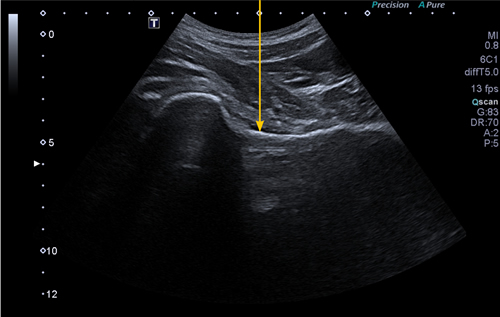

La viscosuplementación intrarticular fue estandarizada en todos los pacientes e independiente del AH empleado. En dicho procedimiento, realizado siempre por los mismos facultativos, se practicaba un abordaje ecoguiado por vía anterior a nivel infrainguinal. Mediante un equipo de ecografía Canon Xario 100G® y con la sonda cónvex de 5 MHz emplazada perpendicular al pliegue de la ingle, y desplazándola lateralmente a los vasos femorales, se identificaba un plano de seguridad que incluyera margen superior de la cabeza y cuello femoral, borde acetabular y recorrido de la cápsula articular hasta la zona cervical del fémur (Figura 1). Mediante el empleo del ecógrafo en su modo doppler podíamos identificar la ausencia de estructuras vasculares en ese plano de seguridad además de medir la profundidad del recorrido de la aguja. En este plano se identificaba el punto medio perpendicular al objetivo de la infiltración en la zona cervical, dentro de la cápsula articular (Figura 2). En ese punto se disponía una aguja espinal de 88 mm y 22 G, en dirección perpendicular al plano de la camilla, desplazándola hasta contactar con el cuello femoral. A continuación se retiraba unos milímetros y se procedía a una aspiración amplia para volver a asegurar la ausencia de estructuras vasculares y eventuales inyecciones intravasculares. Posteriormente se inyectaba el contenido de cada formulación de AH, y se retiraba la aguja colocando un apósito. Todo ello realizado con las adecuadas normas de esterilidad y asepsia. A cada uno de los pacientes se les recomendaba un reposo relativo de 24 horas tras la técnica.

Fig. 1. Imagen de guía ecográfica de la infiltración intrarticular de la cadera, identificándose la cápsula articular en la transición cefálico-cervical del fémur, objetivo para la disposición de la aguja e introducción del producto infiltrado.